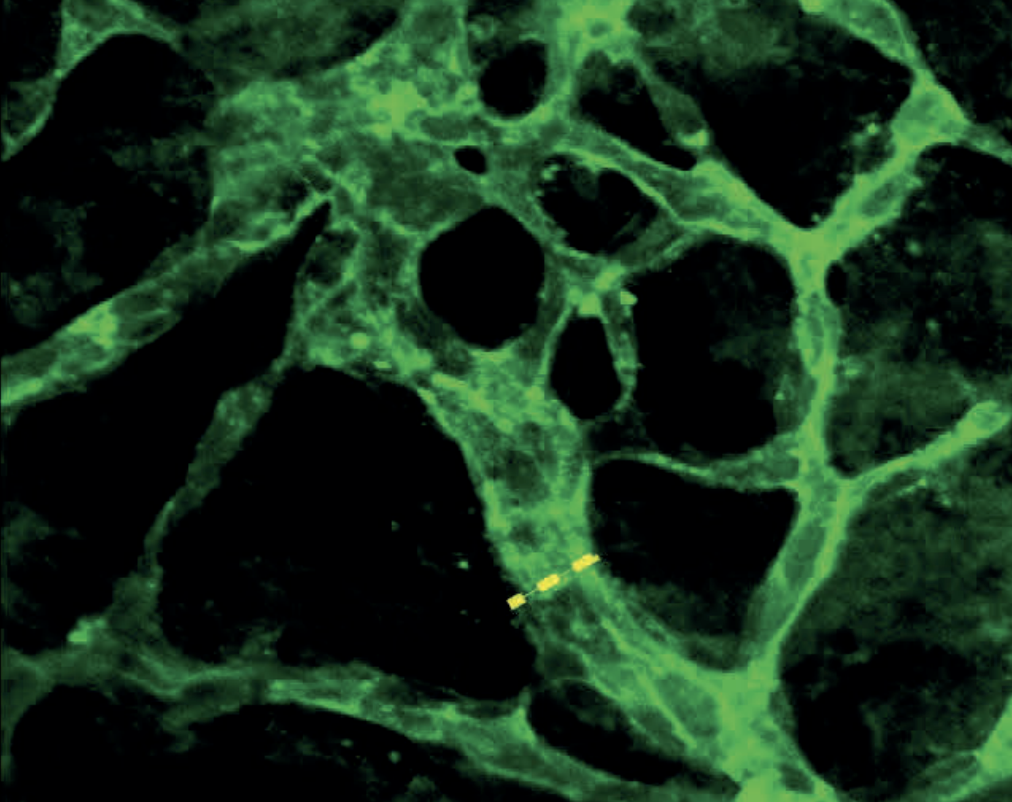

Gallery AV Shunts in P14 MiceMutant P14 Cortex (Glycogen-blue, GFAP-red, and Lectin-green) Prev 1of2 Next